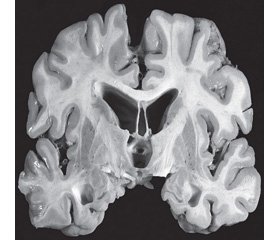

Патоморфологічні макроскопічні прояви хвороби визначаються на рівні органа, тканини або порожнини тіла (рис. 1). Виявляється зниження маси мозку, розширення бічного й третього шлуночків, витончення мозолистого тіла, пориста структура п’ятого шлуночка, рубцювання та втрата нейронів мигдалини мозочка, атрофія лобової, скроневої, тім’яної і, рідше, потиличної ділянок, блідість чорної субстанції та блакитної плями. Зі збільшенням тяжкості захворювання виявляється атрофія гіпокампа, енторинальної ділянки кори і мозочкової мигдалини, нюхової луковиці, таламуса, мамілярного тіла, мозкового стовбура та мозочка.

/22-1.jpg )